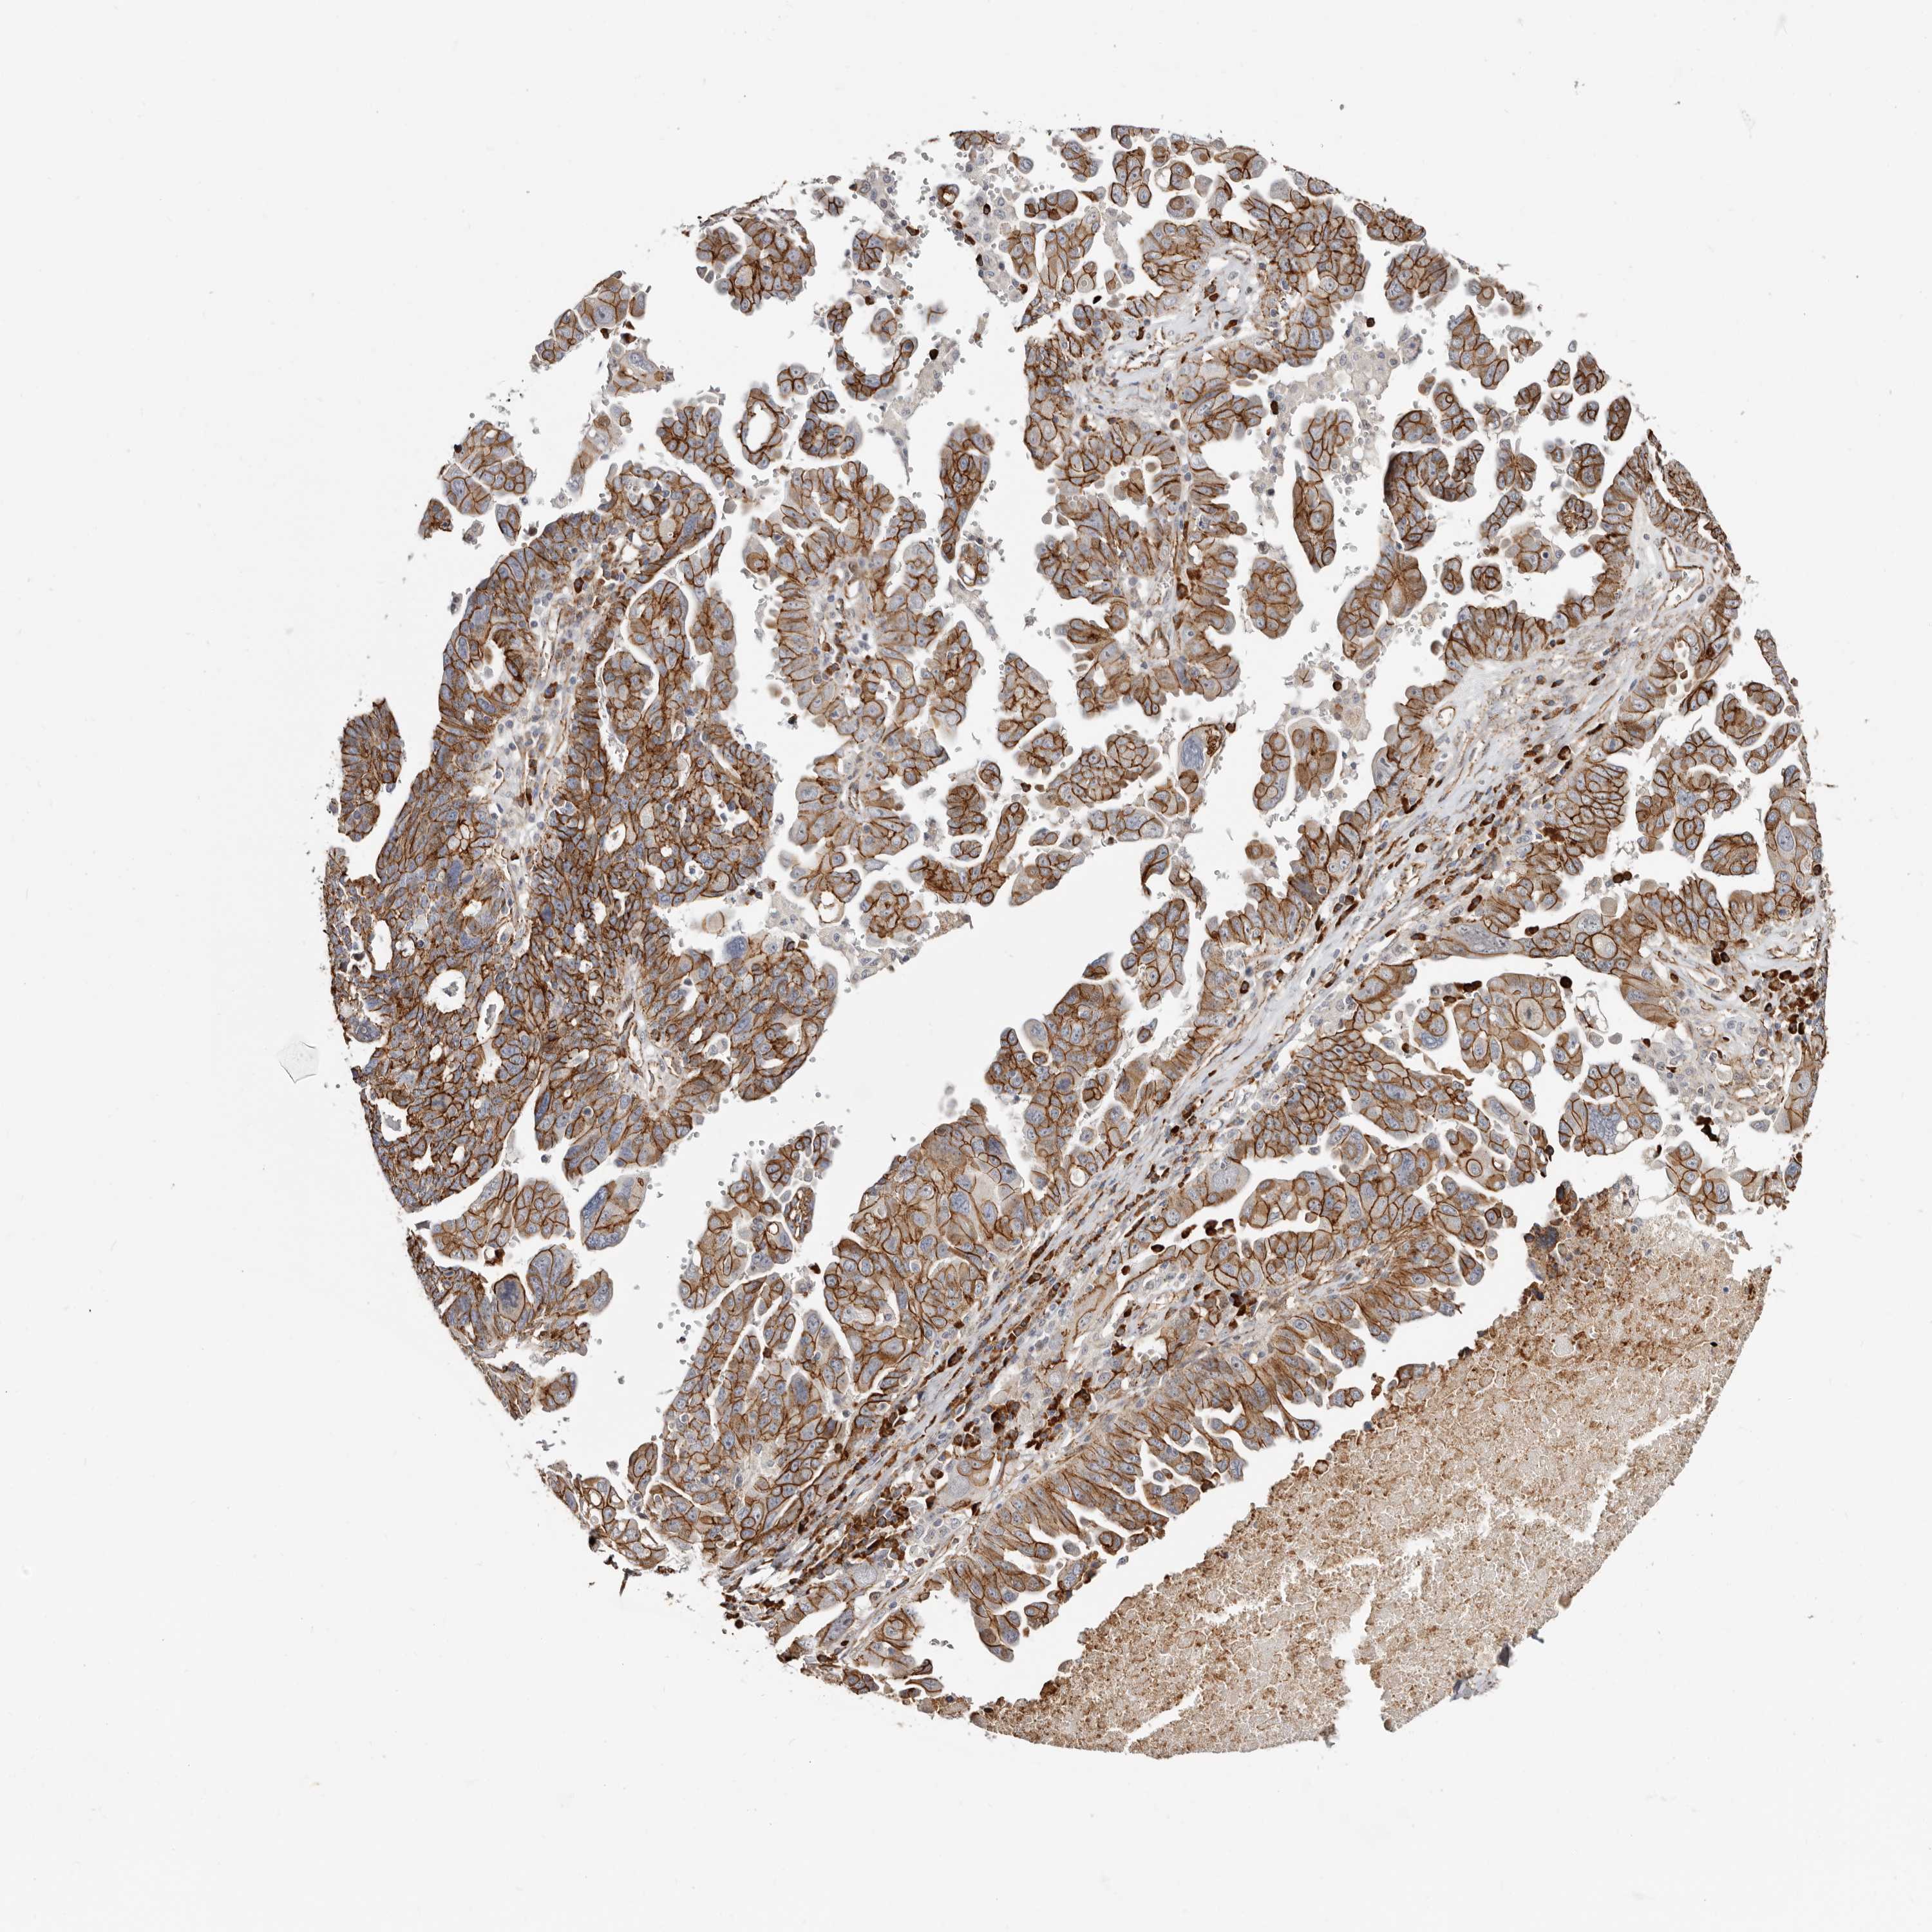

OVARIAN CANCER - Protein expressioni

A mouse-over function shows sample information and annotation data. Click on an image to view it in a full screen mode. Samples can be filtered based on level of antibody staining by selecting one or several of the following categories: high, medium, low and not detected. The assay and annotation is described here.

Note that samples used for immunohistochemistry by the Human Protein Atlas do not correspond to samples in the TCGA dataset.

Antibody stainingi

Antibody staining in the annotated cell types in the current human tissue is reported as not detected, low, medium, or high, based on conventional immunohistochemistry profiling in selected tissues. This score is based on the combination of the staining intensity and fraction of stained cells.

Each image is clickable and will lead to virtual microscopy that enables deeper exploration of all samples and also displays staining intensity scores, fraction scores and subcellular localization as well as patient and tissue information for each sample.

Antibody HPA029159

Antibody HPA029160

Antibody CAB000108

Antibody CAB001950

Staining

High

Medium

Low

Not detected

Cystadenocarcinoma, serous, NOS

Carcinoma, endometroid